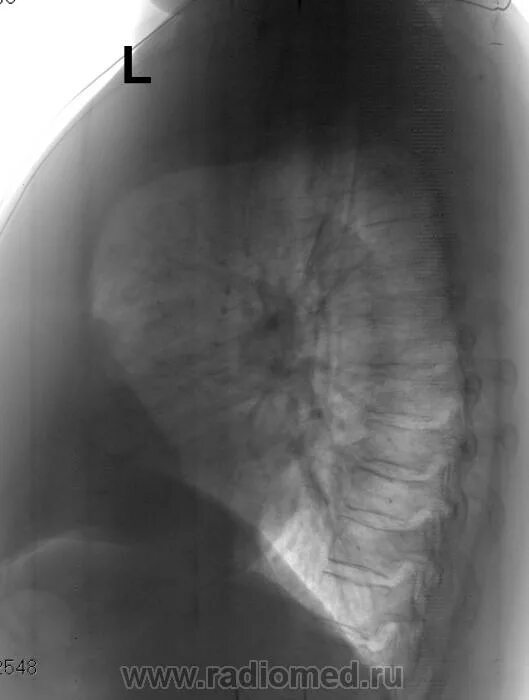

Флюорография в бутово